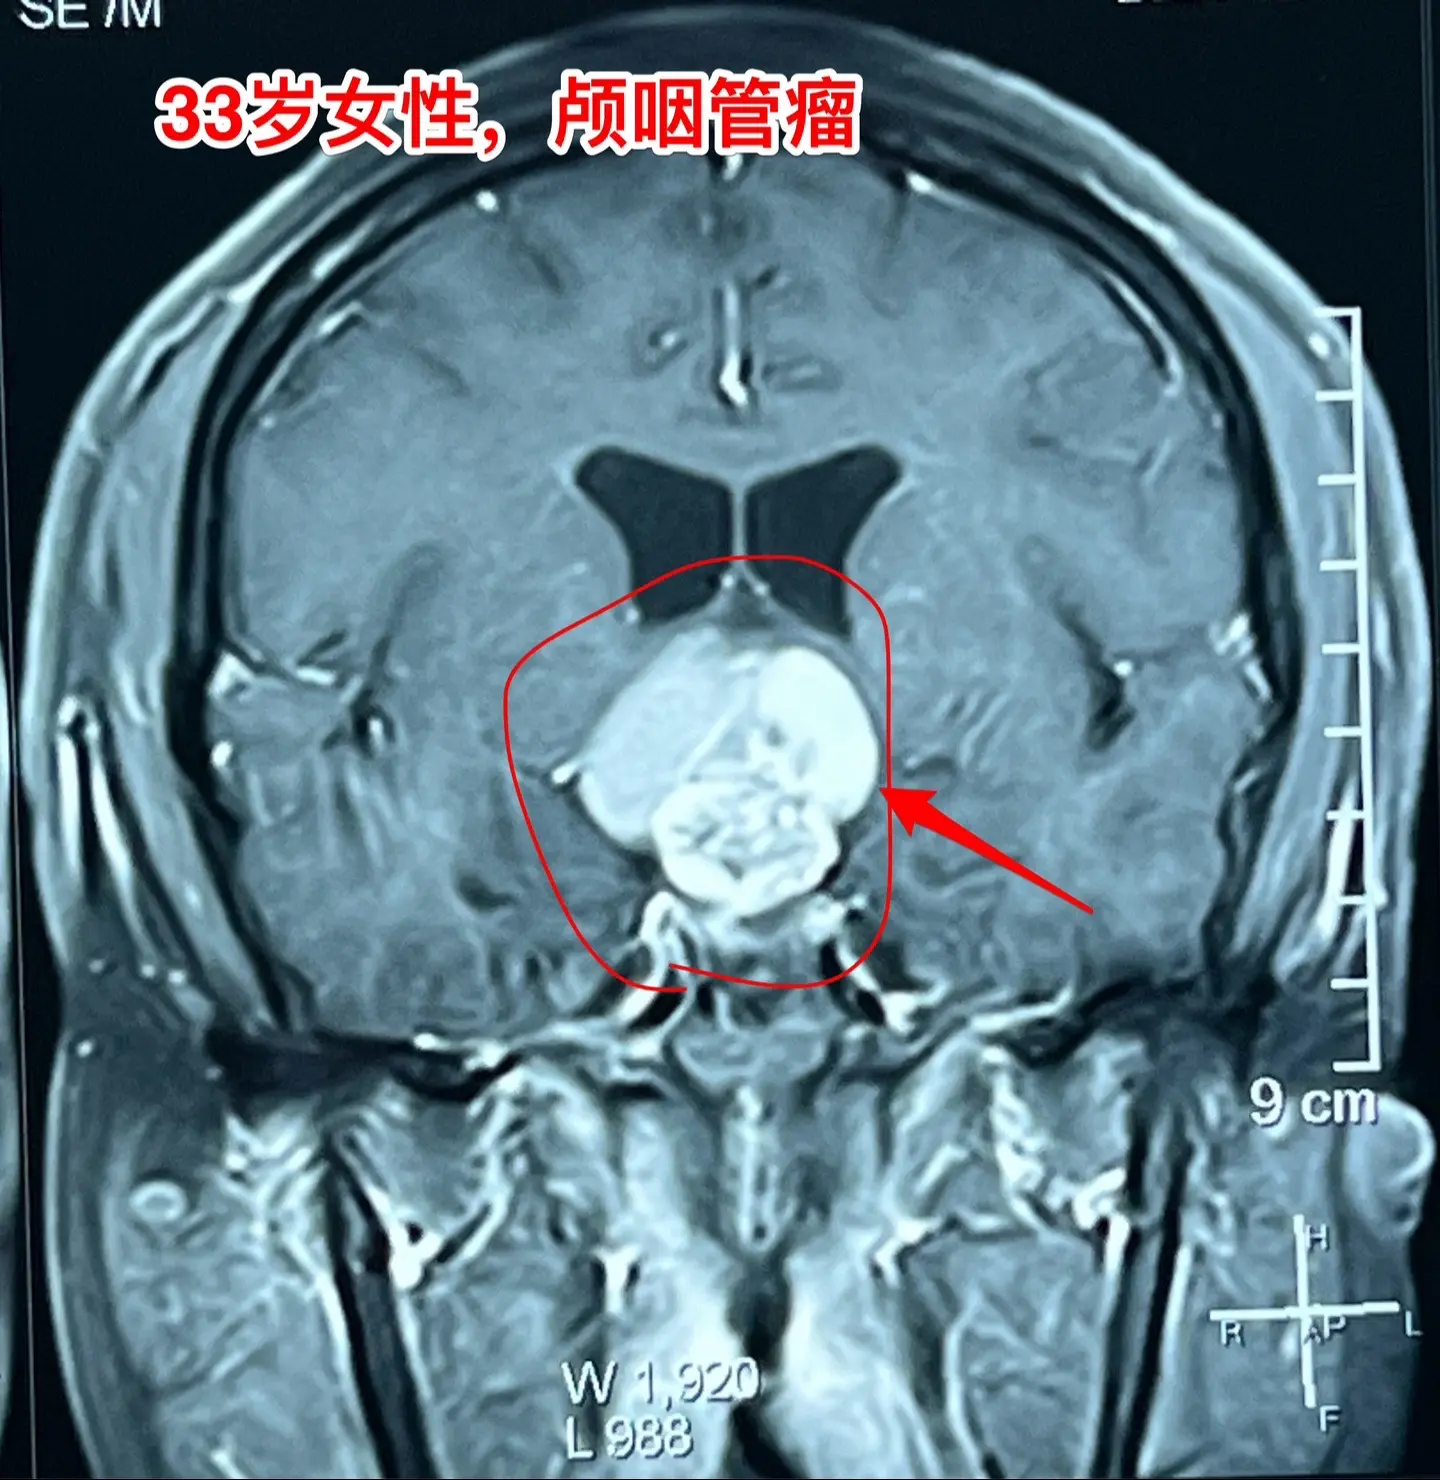

33岁颅咽管瘤患者终于下决心作手术了。洛阳市的女教师,2021年因内分泌紊乱到医院检查,就发现了颅咽管瘤。 由于对手术感到恐惧,再加上工作原因和其他原因,患者一直在观察中,未作手术。 她认识好几个曾经在我这里作过手术的颅咽管瘤病友,每一个成功的手术对她都是一次鼓励! 今年八月份患者和我联系了,说磁共振显示肿瘤在增大,有脑积水了,她也有多睡症状,视力有下降。所以她下定决心要来作手术。 10.28行开颅手术将肿瘤完全切除。肿瘤内有大块钙化,将肿瘤完全切除。手术后患者自述视力有好转。